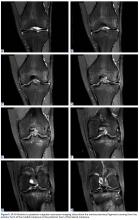

Arthroscopy of the left knee was performed for reconstruction of the ACL and repair of the menisci ( Figures 3, 4 ). The suprapatellar pouch and medial and lateral gutters were normal. There was grade 2 fraying of the distal portion of the trochlea medially and laterally in the medial facet of the patella. An aberrant anterior horn medial meniscus attachment was found; it had been interpreted as a tear on MRI. This aberrancy ran through the femoral intercondylar notch and attached to the posterior horn of the lateral meniscus ( Figures 5A-5H ) ( watch the video ).Discussion

The medial and lateral menisci typically are separate fibrocartilaginous structures acting as a cushion for the knee, but normal variant connections between the structures have been described. These connections include the anterior transverse meniscal ligament, the posterior transverse meniscal ligament, and the medial and lateral oblique meniscomeniscal ligaments. 3 In the present case, a medial oblique meniscomeniscal ligament was identified. Its path between menisci was traceable on coronal and axial views. Video taken during arthroscopy also clearly showed its path and its relationship to other structures in the knee. To Dr. Flanigan’s knowledge, this ligament was not previously described with video. It is important to distinguish this ligament from a horizontal tear of the meniscus, given the potential for misinterpretation on MRI. A horizontal tear is a degenerative change that often occurs in older patients. Our patient was 18 years old at time of injury. In addition, the surface of his lower meniscus was smooth, whereas in a tear the edge is irregular and discontinuous. Dr. Flanigan prefers to leave this ligament intact unless resection would provide better visualization during arthroscopy. His reasoning is that the functional characteristics of the ligament are not well understood.